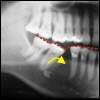

Zahnkippung Die Zähne stabilisieren sich in einer geschloss...

Zahnelongation Eine weitere Folge des fehlenden Zahnes ist, da...

Verzahnung Die Folge von Zahnkippung und Zahnelongation is...